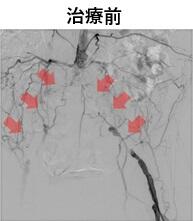

当院で血管内治療を行った閉塞性動脈硬化症の一例